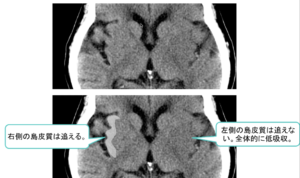

| ③ | ③皮髄境界・島皮質の不鮮明化といった浮腫性変化が発症後2~3時間で出現![]() ![]() |